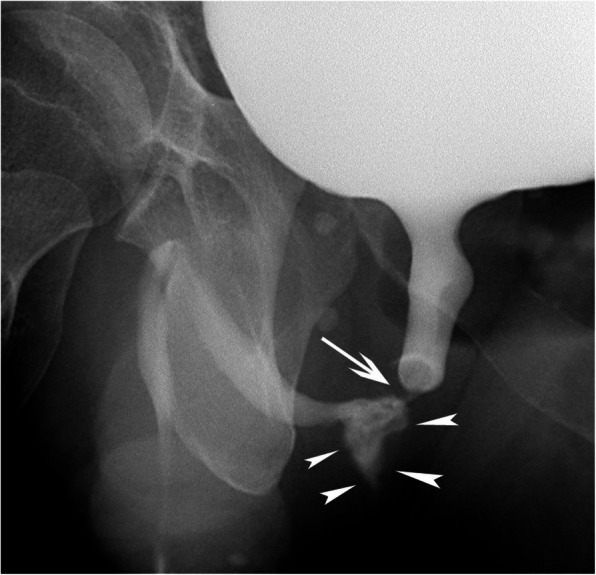

Background: Urethral bleeding can be related to iatrogenic and non-iatrogenic trauma; selective internal iliac angiography may identify contrast extravasation with or without a pseudoaneurysm at the level of the distal internal pudendal or bulbourethral artery. Here, we describe another, yet unreported vascular lesion of the bulbourethral artery related to urethral injury.

Case presentation: Two patients with a iatrogenic and non-iatrogenic urethral bleeding respectively are presented. Conservative management, including Foley catheter placement and endoscopic management were unsuccessful. Selective internal pudendal angiography revealed an arteriospongious fistula without clear contrast extravasation into the urethral lumen; super-selective embolization with microcoils and non-adhesive liquid embolics was safely performed and successfully stopped the bleeding. The postinterventional course was uneventful and both patients recovered without sequelae.